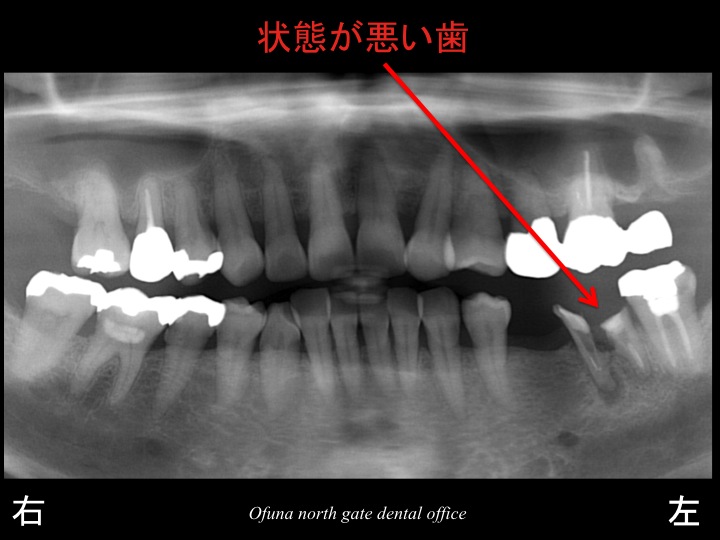

特に今回のケースの場合には、ブリッジは適していません。

その理由として、欠損部の奥歯の状態が悪いからです。

この奥歯の状態から考えると

もし、今回ブリッジを行ったとしても

その将来性は低いと考えられます。

そのため、今回のようなケースでは、

インプラント もしくは 義歯が適しているでしょう。

先程もご説明したように欠損部の奥の歯は、あまり良い状態とは言えません。

そのため、この歯は抜歯とした方が将来性は高いと言えます。